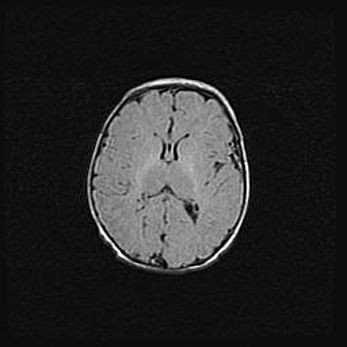

Сообщающаяся гидроцефалия. Кистозная энцефаломаляция головного мозга.

Возраст: 3 месяца 4 дня

Вес: 3100 г

Пол: женский

Окружность головы: 34 см

Срок гестации: 31 неделя

Кистозная энцефаломаляция головного мозга - одна из форм поражения головного мозга в детском возрасте. Характеризуется возникновением множественных и распространённых кист в коре, белом веществе и подкорковых образованиях головного мозга у плодов, новорождённых и детей раннего возраста. Развитие кистозной энцефаломаляции связано с внутриутробной асфиксией и гипотонией, родовой травмой, тромбозом синусов, пороками развития сосудов, инфекциями, сепсисом и другими причинами. Наиболее значимые инфекционные агенты: вирусы простого герпеса, цитомегалии, краснухи, токсоплазмы, энтеробактерии, золотистый стафилококк и другие.